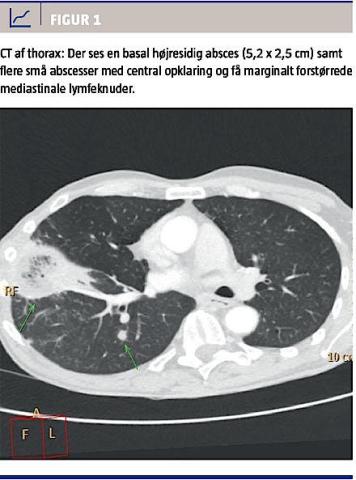

En røntgenundersøgelse af thorax afslørede et basalt højresidigt infiltrat. En transtorakal ekkokardiografi viste en sklerotisk aortaklap uden tegn til endokarditis. En CT af thorax viste en absces på 5,2 × 2,5 cm i nederste højre lungelap (Figur 1). Der fandtes leukocytose (14,0 (109/l)) samt forhøjet C-reaktivt protein (210,5 mg/l).